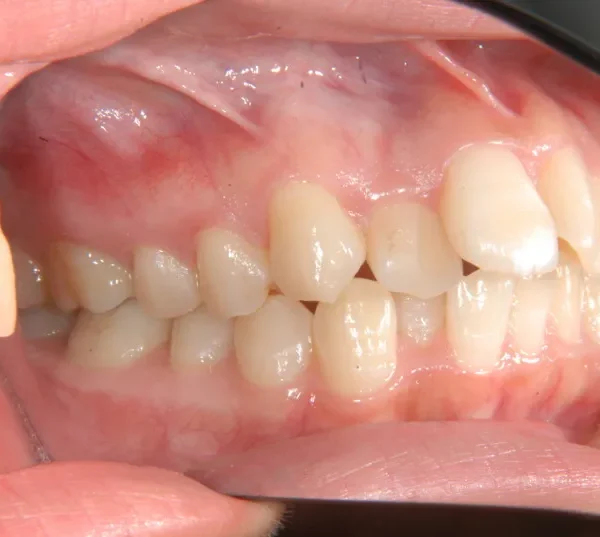

治療回数○回、2年9ヶ月の治療期間で矯正治療を終了しました。

主訴が改善され、ご満足頂きました。

治療経過1